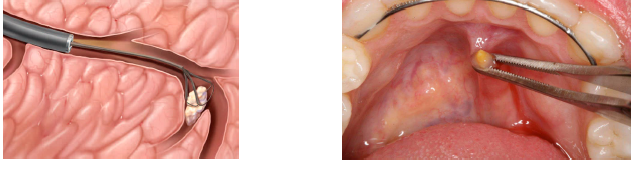

sialolithiasis (salivary stone) treatment

can sometimes be worked toward the orifice and “passes” by heat, increased fluid intake, and milking/massaging of the gland

lithotripsy (shock waves break up stone into smaller pieces that can be passed)

surgical removal is often indicated

the associated gland may also need to be removed if significant inflammatory damage has occured